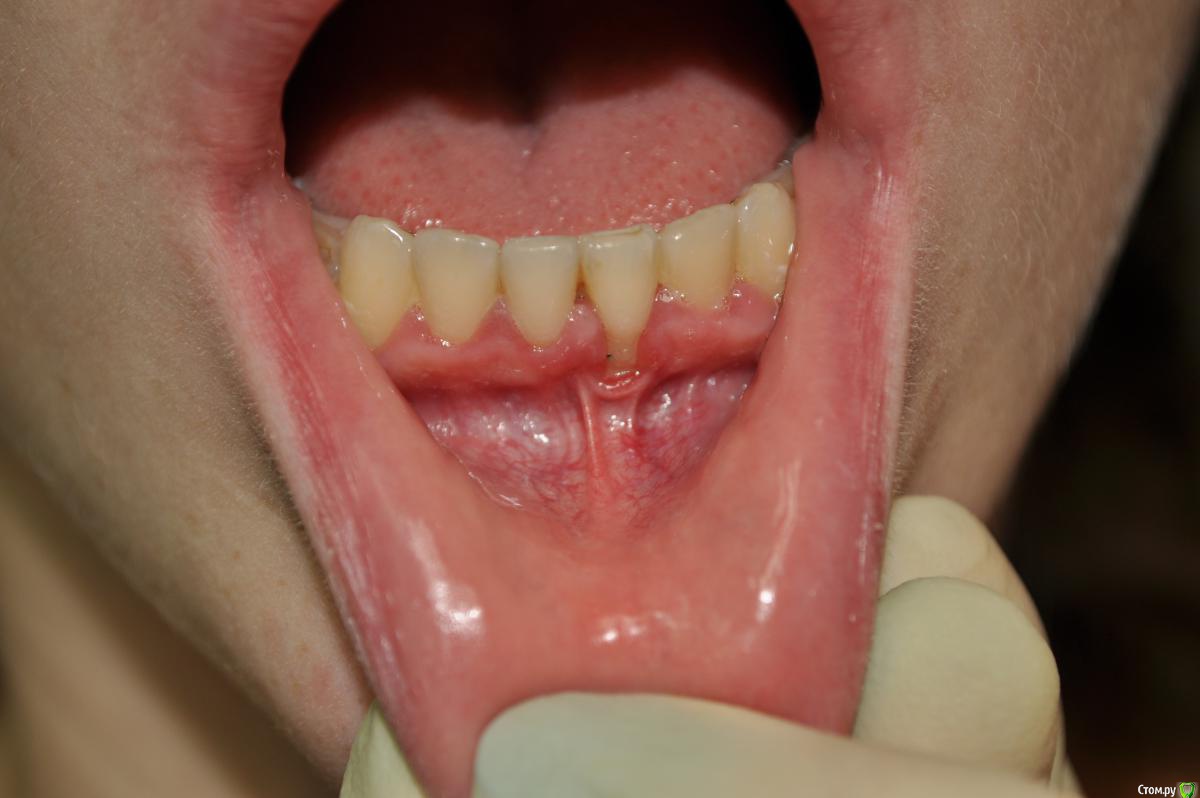

IshIm0 Опубликовано 1 апреля, 2016 Поделиться Опубликовано 1 апреля, 2016 Добрый день коллеги. Девочке 24 года, 1.5 года после ортодонтического лечения, пол года назад заметила рецессию. Как я думаю: 1 этап - вестибулопластика. 2 этап - через пол года забор сст с неба и устранение рецессии. Восьмерку кстати тоже удалять нужно. Поделитесь своим ви'дением этой ситуации, советами, "подводными камнями" ) Все ли верно по срокам? Ссылка на комментарий

CrazySonic Опубликовано 1 апреля, 2016 Поделиться Опубликовано 1 апреля, 2016 ну если не вестибулопластика то пластика уздечки точно нужнапо срокам док верно мыслит Ссылка на комментарий

Artem_MD Опубликовано 1 апреля, 2016 Поделиться Опубликовано 1 апреля, 2016 проф гигиена, кюретаж, через 2-3 недели если воспаление уйдет полностью сст в конвертеникаких пластик уздечек и преддверия не делайте, только рубцов лишних оставите. Ссылка на комментарий

Доктор Добрых Дел Опубликовано 1 апреля, 2016 Поделиться Опубликовано 1 апреля, 2016 Уздечка там вообще не при делах. Закрыть штанами и все дела. 2 Ссылка на комментарий